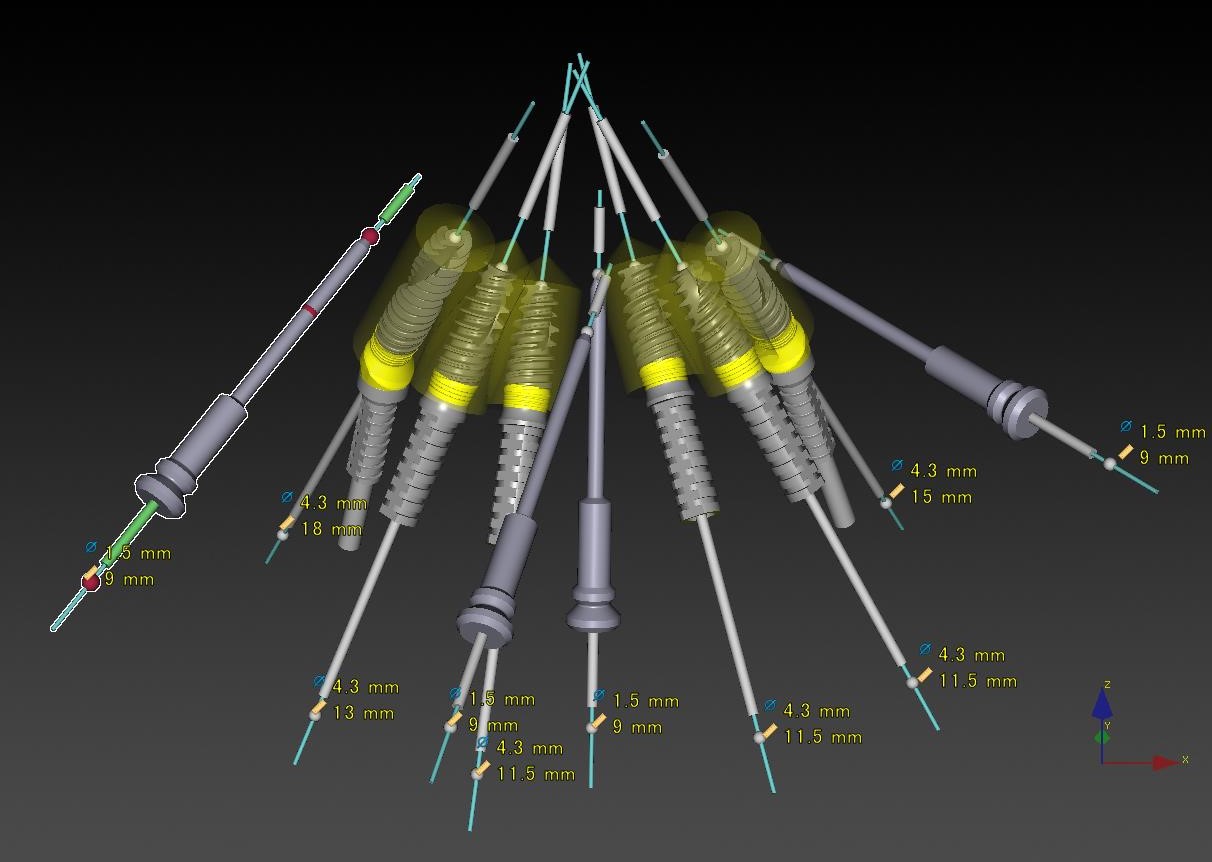

症例11

50代 男性 なんでも食べられるようになりたい

術前シミュレーション1

術前シミュレーション1

術前シミュレーション2

術前シミュレーション2

サージカルテンプレート

サージカルテンプレート

| 主訴 | 自分が一番元気に、何でも食べられる父親でいたい。家族との食事の時間が人生ですごく大切で、何とかしたい、と思っていた。 |

|---|---|

| 年代・性別 | 50代 男性 |

| 治療部位 | 上顎6~6 |

| 治療費用 |

インプラント手術料 |

| 手術回数 | 1回 |

| 治療期間 | 4ヶ月 |

| 手術時間 | 180分 |

| 治療回数 | 10回 |